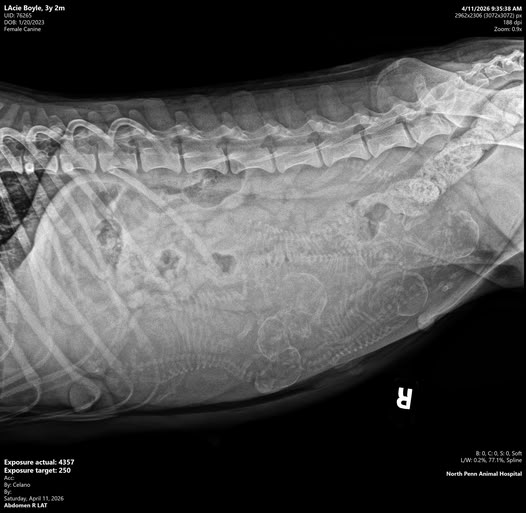

Lacey X Winston Litter ~ Five Females, 1 Male Reserve your puppy now

Contact Gloria Boyle 610-762-0524 or gloria.boyle821@gmail.com

Stone Run Late For Tea "Lacey"

CH Stone Run J-Bird Winston Churchill "Winston"